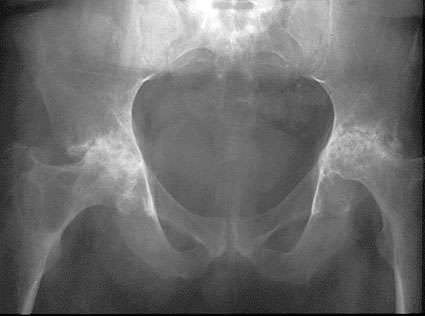

Rheumatic arthritis causes joint erosion and joint destruction visible on x-rays and symptoms that can be severe and limiting. As the joint becomes eroded the cartilage is damaged and the articulation of bone-on-bone causes severe pain. Damage to cartilage, tendons, ligaments and bone causes the hip joint to become deformed and even unstable as rheumatoid arthritis progresses.

The frequency of acetabular protrusio is higher in rheumatoid hips as is the likelihood of significant femoral head deformity. Bone quality is poor especially in those patients who have needed long term steroid treatment. This makes these operations more difficult, with a higher risk of per-operative and post-operative complications.